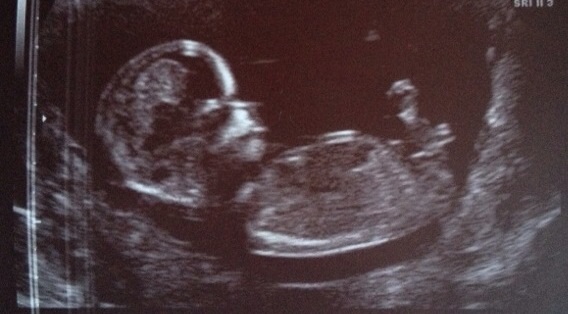

I think boy

Boy, I see 2 dots on the nub! I hope this is what u were hoping to hear!

I hate to say it but I guess girl for two reasons. One is it looks less than 30 degrees relative to the spine and also it has the "fork" at the end and many believe this indicates girl. I'm sorry if you wanted to hear boy and yay if you wanted to hear girl. Either way I hope you get the gender you are hoping for.

Praying in pink, are you sure that's a fork? It looks like the classic 2 boy dots to me! I can see how it may be a bit tricky, b/c the nub is longish like a girl but has the 2 dot boy rise...it doesn't look like a fork to me at all! It looks very much like the example boy nubs on here http://genderdreaming.com/forum/ultr...bs-inside.html.

ETA: I just compared this nub to my DS3's and the angle is the same (my DS3's nub was from late in the 12th week). I got 50/50 boy and girl guesses with his. Now, the OP's is a tiny bit longer than my DS3's but the 2 dot/2 lines above the end screams penis to me lol!!!

I would say boy